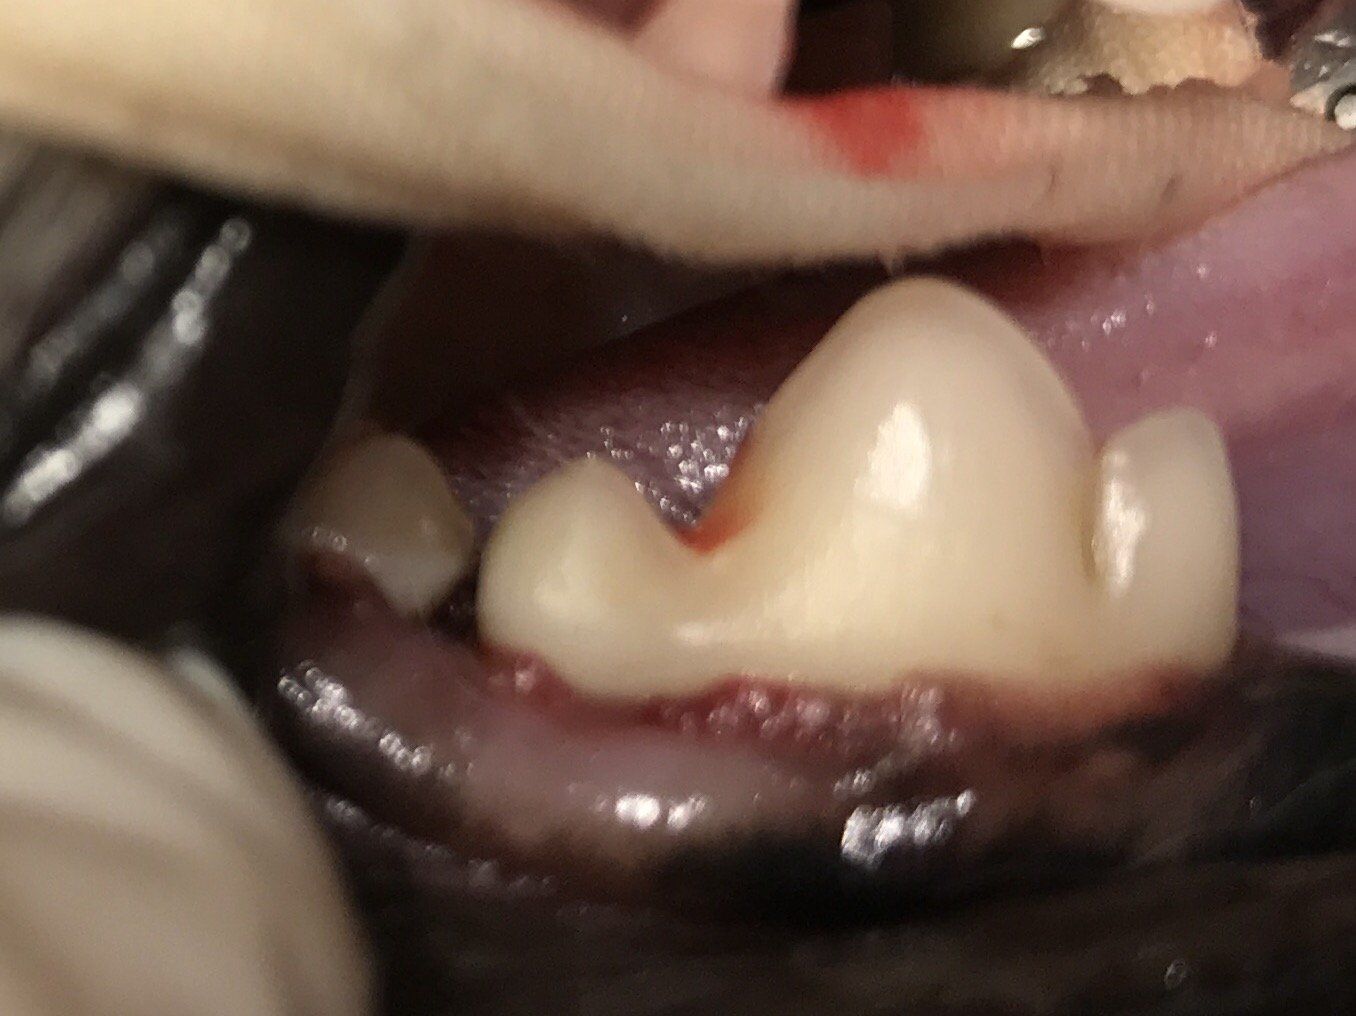

Wortelpunten verwijderen, na een niet goed uitgevoerde totale gebitsextractie, bij de kat

Op foto 1 en 3

zie je een heel erg ontstoken bekje, het tandvlees in de hele bek is vurig rood en super pijnlijk.

Op foto 5 en 6

zie je het resultaat, netjes gehecht en alle wortelrestanten, snijtanden en hoektanden eruit. 80 % van de katten geeft hierna een heel goede verbetering, bij 20% is de verbetering onvoldoende en is verdere behandeling met medicijnen nodig.

Eten geeft geen problemen zonder tanden en kiezen, muizen vangen wordt wel lastiger...